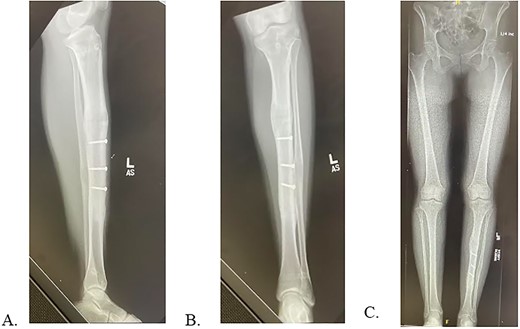

The patient had first presented to the orthopedic clinic at age ten due to limb length discrepancy (LLD) causing a progressively worsening limp. Initial hip to ankle scanogram identified that the left lower extremity (LLE) was shorter than the right by 3.1 cm (Fig. 1A). The patient underwent distal femoral and proximal tibial epiphysiodesis for the right lower limb with no complications. A year later the LLE was 2.5 cm shorter than the right (Fig. 1B). The patient then underwent left tibia and fibula osteotomy with insertion of a bone lengthening intramedullary rod which lengthened by 0.25 mm ×3 a day for eight weeks (Fig. 1C). A delayed union was identified nine months after the lengthening procedure indicating explantation of the two distal and one proximal interlocking screw for dynamization (Fig. 1D). Following the surgery, the patient recovered with osseous union, decreased pain, and improved gait (Fig. 1E).

A: 10.5-year-old female with fibular hemimelia, affected left side. B: 11-year-old female status post right distal femur and proximal tibia epiphysiodesis. C: 8-weeks status post left tibia/fibula osteotomy and PRECICE implantation. D: 9-month postoperative PRECICE implantation of left tibia with delayed union. E: 3-months postoperative dynamization of left tibia with osseous union.